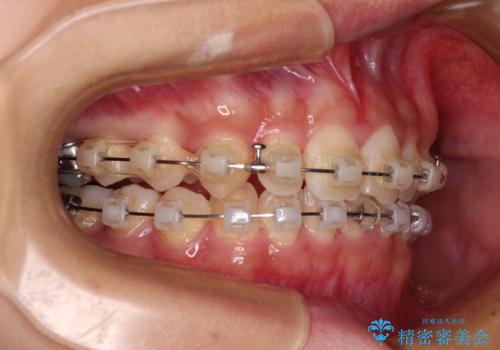

- 矯正装置

- クリアブラケット

- 前歯のデコボコと深い咬み合わせを改善したいとのことで来院された患者様です。

奥歯の咬み合わせは上顎に対して下顎が後方位にあり、上顎前歯で下顎前歯が隠れるような典型的な過蓋咬合です。

補助装置を用いて上顎大臼歯を後方に移動させながら、ワイヤー装置で歯列を整えて深い咬み合わせを挙上することとしました。